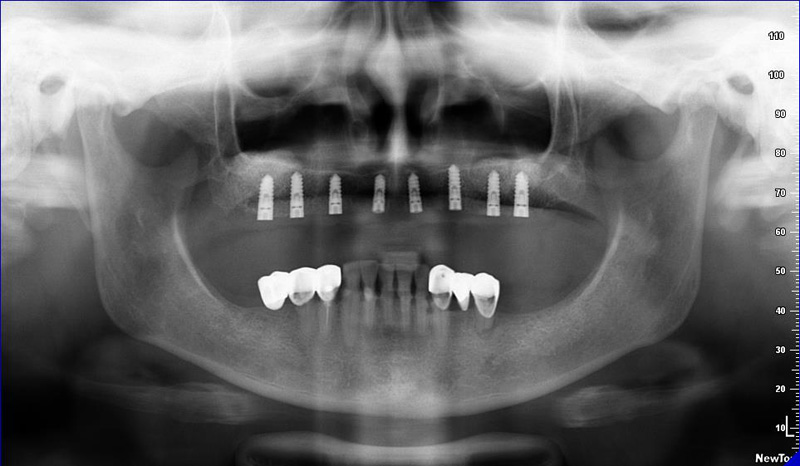

Zásadním faktorem pro úspěšné ošetření je přesná a detailní diagnostika a dokonalé naplánování celého ošetření. K tomu vždy využíváme kombinaci zjištění z klinických vyšetření a rentgenologických dat, které následně zpracováváme v plánovacím softwaru.

Jak pro ošetření stomatochirurgická tak implantologická spolu různými dostavbami kosti je vždy nutné předem znát umístění důležitých anatomických struktur (cévy, nervy, čelistní dutiny). Naše pracoviště jako první v České republice začalo

od roku 2004 používat speciální digitální zubní tomograf 3D DVT NewTom a dále také využíváme nejnovější hybridní CBCT (3D) + 2D přístroj NewTom GiANO, které umožňují 100% diagnostiku množství a kvality kosti a veškerých důležitých anatomických struktur.

Pro následné plánování využíváme počítačové programy NewTom Implant Planning a coDiagnostiX, které slouží na plánování vhodných pozic pro zavedení implantátů, operačních šablon, kostních bloků, pozdějších protetických náhrad, ...

Jedná se o nejnovějším přístroj ze skupiny dentálních hybridních CBCT (3D) + 2D (pan i ceph) systémů. Přístroj umožňuje na základě jediného snímkování vytvořit všechny typy RTG zobrazení, které jsou pro lékaře potřebné.

Používaná technologii tzv. „kuželového paprsku“ a speciální senzory pro minimální zátěž při snímkování pacienta

(o více jak 80% nižší dávka proti klasickému CT).

Pomocí tohoto přístroje je možné zjisti skutečnou situaci v čelistních kostech pacienta tedy množství kosti - můžeme změřit skutečnou šířku i výšku kosti, i kvalitu kosti (hustotu) v místě uvažované implantace. 3D (tříprostorové) zobrazení umožňuje

zvýšit prostorovou představu operatéra ještě před vlastní operací a zároveň pacientovi lépe objasnit a ukázat oblast plánovaného zavedení implantátu.